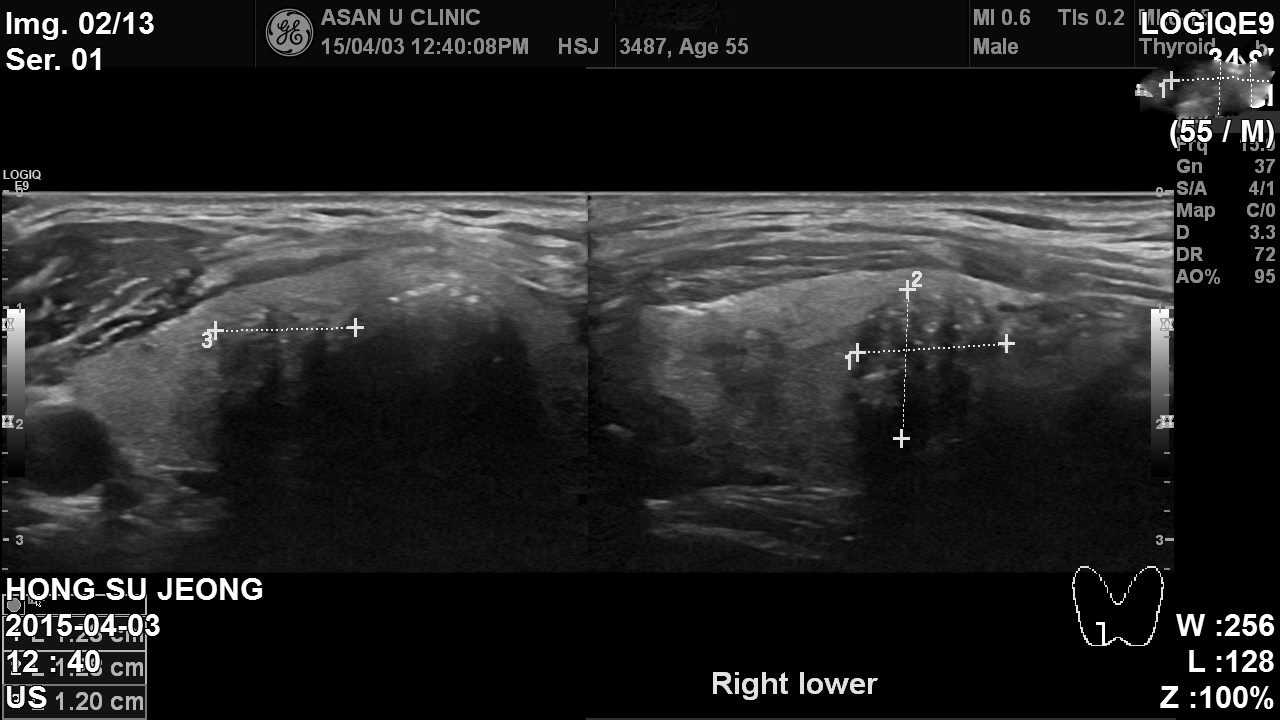

아산유외과 개원 후 26번째 갑상선암 진단.

지난해에  여론몰이로, 착한암으로 분류되어 과잉진료의사 논란이 있은후

갑상선암검사가 급격히 줄었습니다. 오랜만에 갑상선암 진단 증례입니다.

놀랍게도 50대 남자분 이고요. 이처럼, 당연히 남자들도 갑상선암이 걸릴수 있습니다.